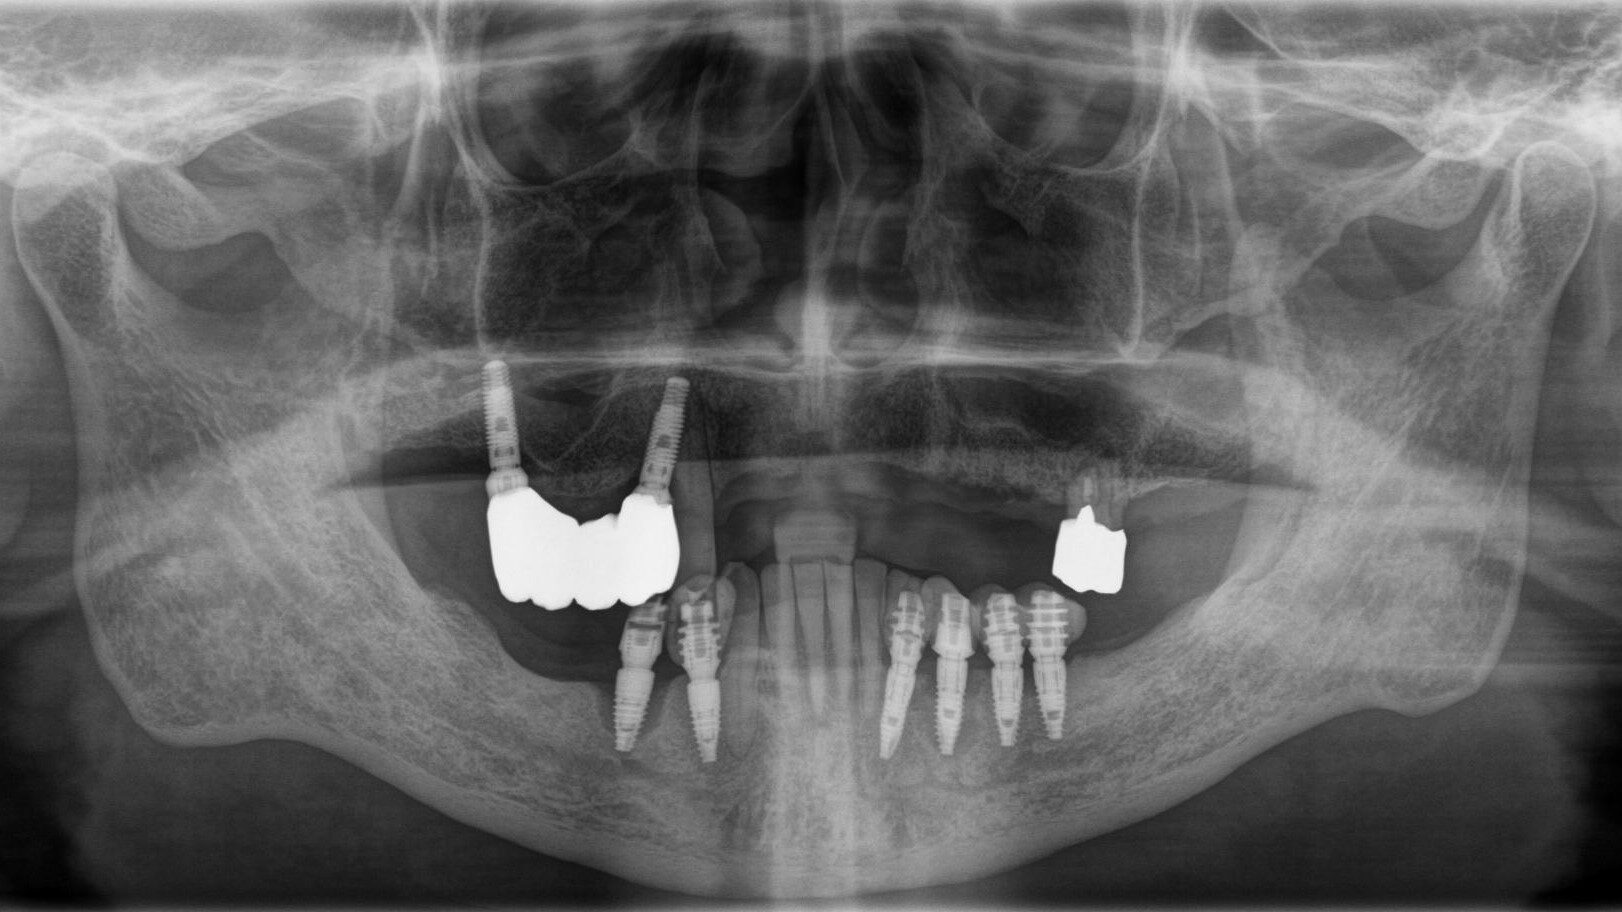

歯科医院にインプラントを相談しても「骨が全くない」「入れ歯しか無理」「オーバーデンチャー」と言われた患者さんのレントゲン画像です。

手術終了 術後ですが静脈鎮静麻酔なので意識が聡明になるのがとても早いです。小休憩後、術後のパノラマX線の撮影を行い、インプラントが適正な位置に施術できているかを確認します。その後、噛み合わせの調整などを行います。当日にお帰り頂き翌診療日に傷口の確認をさせていただきます。